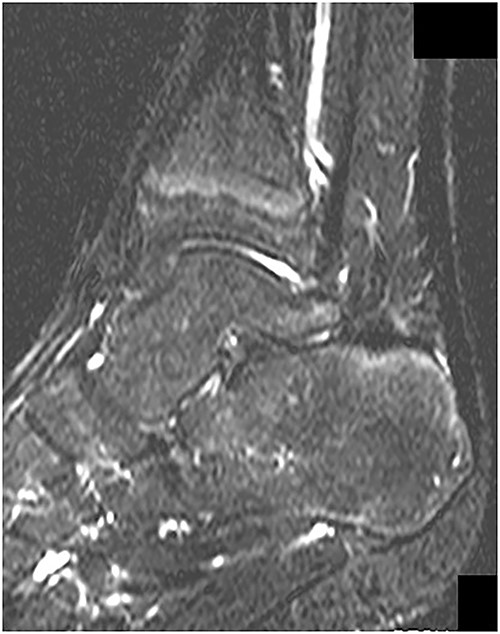

MRI revealed no abnormal signs on short TI inversion recovery images at 1 year postoperatively.